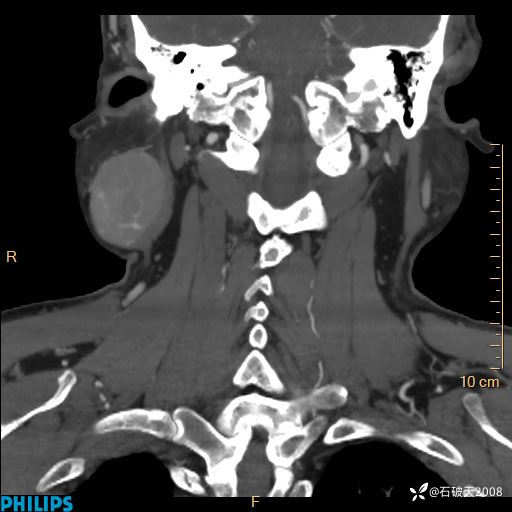

动脉期